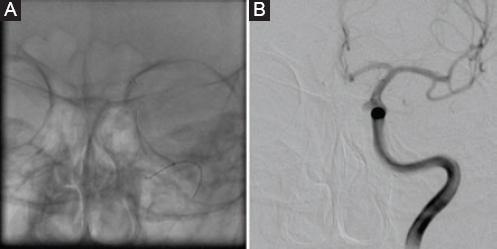

Con antiagregación plaquetaria intravenosa (tirofibán) se colocó una endoprótesis Solitaire™ AB de 4 × 30 mm (Fig. 2).

Figura 2 A y B: se observa la endoprótesis liberada posicionada desde el segmento C4 al C7 de la arteria carótida interna izquierda.